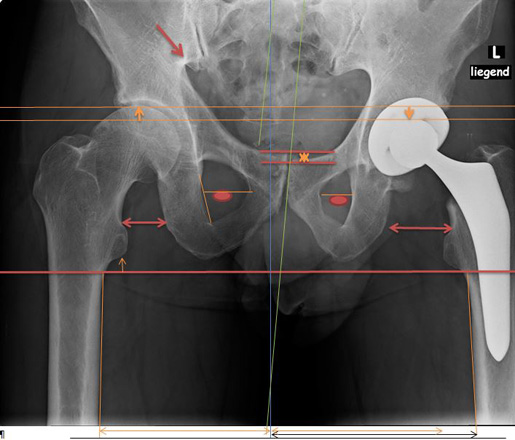

1.2

Wurde ein neues Hüftgelenk eingebaut, wegen den Schmerzen in der Leiste.

1.3

Nun sieht man, dass die Bein- und Gelenk-Stellung nicht übereinstimmt.

Die Schmerzen sind geblieben.

Abbildung Hüft / Teil Rücken / Teil Beine von hinten aufgenommen

1.5

1.6

Hüft mit Strichen Pfeilen Kreise sichtbar gemacht

Oberkörper weicht trotz Hüftgelenk Ersatz blau eingesetzte Striche aus.

Anhand der Gesässfalten wird auch der Beckentiefstand ersichtlich.

Über die Grüne Linie sieht man wie die rechte Seite geknickt wird.

Auf der linken Seite wird die Überdehnungsspannung sichtbar.

Würde die Ganz-Körper-Statik Vermessung eingesetzt, würde die Diagnose schnell und präzise die Ausweichhaltungen aufzeigen.

Würde die Ganz-Körper-Statik Vermessung bei den bildgebenden Verfahren eingesetzt, könnten Fehldiagnosen verhindert werden. Dies würde die Ursache der Skelett Ausweichhaltungen als Ursache der Muskelfehlspannungen aufzeigen.

1.7

Trotz dem wurde das andere Hüftgelenk auch noch ausgewechselt.

Trotz Operationen sind die Schmerzen geblieben.

Beachtet man das Becken und die Gelenk-Stellungen sieht man nun auf der rechten Seite eine Verdrehung des Beckenlochs.

Der Beckenspalt ist immer noch hochgezogen. Durch die Verdrehung quetscht nun die linke Seite.

Man hat die Belastung verschoben.

Bei der Statik Kontrolle wurde der Beckentiefstand und der damit verbundenen seitlichen Oberkörper- Ausweichhaltung nicht beachtet.

1.8

DICOM-30

Würde die Ganz-Körper-Statik Vermessung bei den bildgebenden Verfahren eingesetzt, könnten Fehldiagnosen verhindert und zudem viele Kosten gespart werden. Dies würde die Ursache der Skelett Ausweichhaltungen als Ursache der Muskelfehlspannungen aufzeigen.